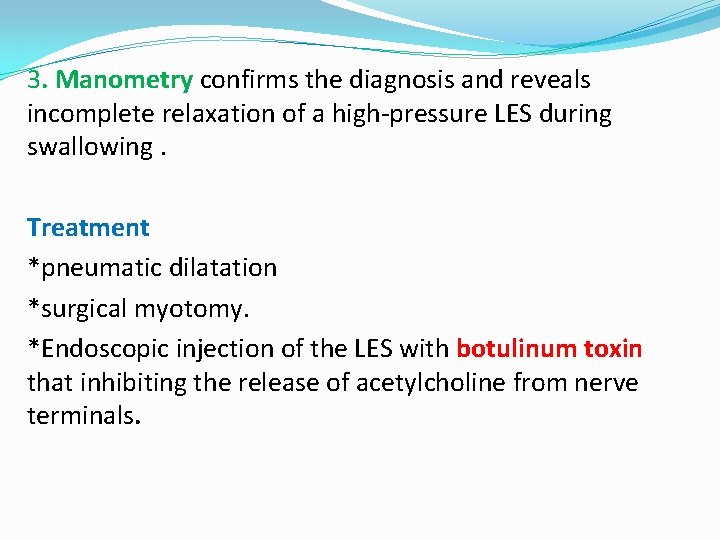

3. Manometry confirms the diagnosis and reveals incomplete relaxation of a high-pressure LES during swallowing. Treatment *pneumatic dilatation *surgical myotomy. *Endoscopic injection of the LES with botulinum toxin that inhibiting the release of acetylcholine from nerve terminals.